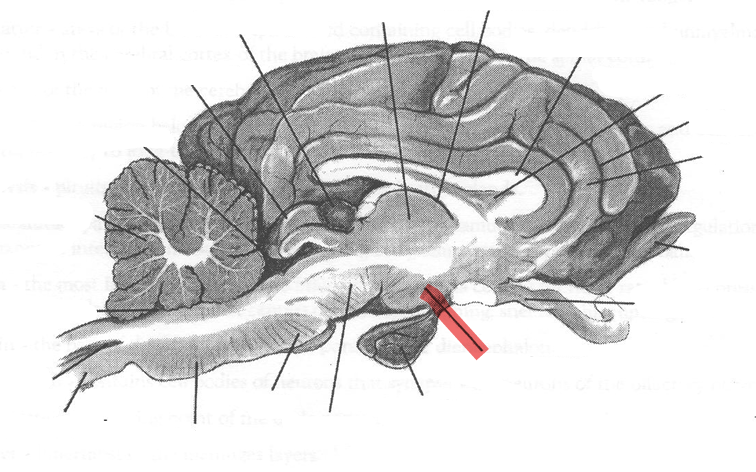

Identify highlighted arrow

Spinal cord

2

New cards

Identify highlighted arrow

Medulla

3

New cards

Identify highlighted arrow

Pons

4

New cards

Identify highlighted arrow

Midbrain

5

New cards

Identify highlighted arrow

Hypophysis

6

New cards

Identify highlighted arrow

Hypothalamus

7

New cards

Identify highlighted arrow

Optic nerve

8

New cards

Identify highlighted arrow

Olfactory bulb

9

New cards

Identify highlighted arrow

Gyrus

10

New cards

Identify highlighted arrow

Sulcus

11

New cards

Identify highlighted arrow

Corpus callosum

12

New cards

Identify highlighted arrow

Third ventricle

13

New cards

Identify highlighted arrow

Thalamus

14

New cards

Identify highlighted arrow

Pineal body

15

New cards

Identify highlighted arrow

cerebellum

16

New cards

Identify highlighted arrow

Fourth ventricle